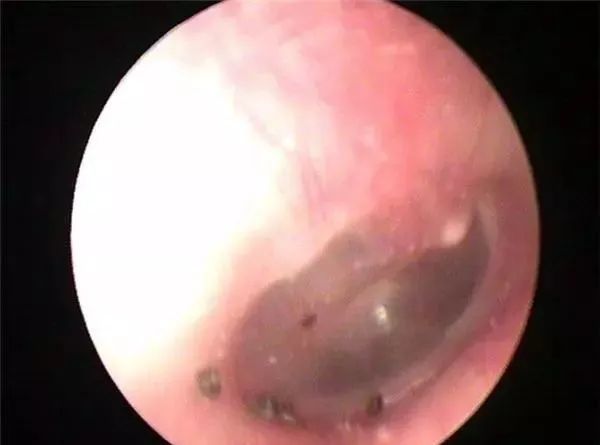

耳内镜检查图片

小虫被取出

值得庆幸的事,这只蠼螋并没有对李女士的耳膜造成破坏,只是引起了局部充血红肿,因治疗及时,李女士很快便离开了医院。